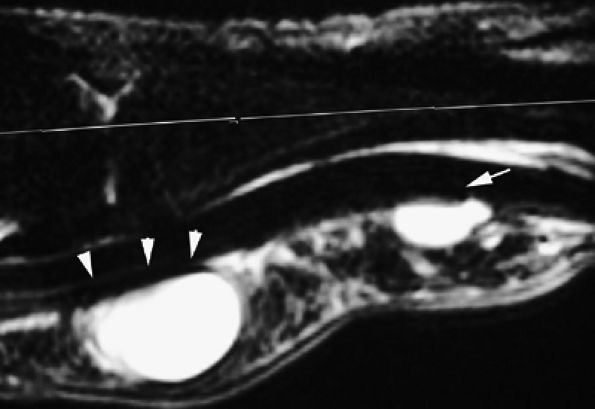

FIGURE 11.47 ● Jersey finger. (A) Sagittal T2-weighted image. (B) Coronal post-contrast T1-weighted images. (C) Axial T1-weighted image. Distal avulsion of the FDP tendon is shown with the proximal end (white arrows) at the metacarpophalangeal joint (type I). The tendon is wavy in the palm (arrowheads). The empty digital canal (in C) may mimic a remnant tendon, but the FDS tendon (asterisk) is alone in the canal.